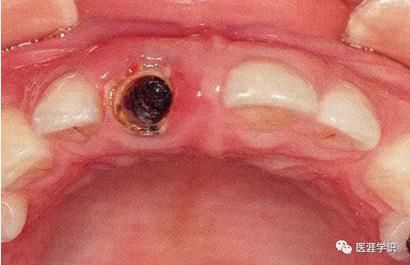

圖3-3,4 由于牙體缺失使牙槽突起造成了一定吸收,但是可以靠降低拔牙時的傷害,來盡可能的保留舌側(cè)牙槽突起。其結(jié)果就是多多少少防止了牙槽骨的吸收。